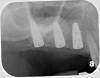

Drill depth gauge—A common complication of the crestal drill osteotomy is unintended perforation of the Schneiderian membrane. As a consequence, specific sleeves in different lengths were developed (Figure 8). These sleeves, which are placed on the drills, serve as gauge stoppers that prevent drill overextension. While the Cosci system uses only 3-mm-diameter drills, the newer systems include wider-diameter drills, which offer better visibility and control of the osteotomy and the integrity of the Schneiderian membrane. Figure 9 shows an implant insertion case using one of the newer systems to perform this crestal osteotomy technique. Osteotomy was performed with a non-cutting drill in 1-mm depth increments using depth gauge stoppers until the bone tissue is removed and the intact Schneiderian membrane is visible. The Schneiderian membrane is then elevated using bone-filling material, as described by Summers’ original technique (Figure 10). Following sufficient augmentation, the implants are inserted (Figure 11). Cone-beam computed tomography after 6 months reveals the bony mantle covering the inserted implants (Figure 12).

Fig 9. Crestal approach to sinus floor augmentation using special drill system. Osteotomy was carried out with drills in 1-mm-depth increments using depth gauge stoppers, until the intact Schneiderian membrane is visible.

Fig 10. The Schneiderian membrane is separated and elevated from the sinus floor using bone-filling material.

Fig 11. Dental implants are inserted through the crestal osteotomy preparation.

Fig 12. Cone-beam computed tomography 6 months after the procedure reveals the bony mantle covering the inserted implants.